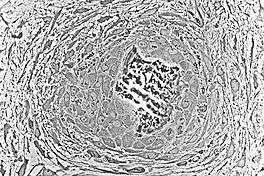

As the spicules continue to grow, they fuse with adjacent spicules and this results in the formation of trabeculae. When osteoblasts become trapped in the matrix they secrete, they differentiate into osteocytes. Osteoblasts continue to line up on the surface which increases the size. As growth continues, trabeculae become interconnected and woven bone is formed. The term primary spongiosa is also used to refer to the initial trabecular network.

Osteons are components or principal structures of compact bone. During the formation of bone spicules, cytoplasmic processes from osteoblasts interconnect. This becomes the canaliculi of osteons. Since bone spicules tend to form around blood vessels, the perivascular space is greatly reduced as the bone continues to grow. When replacement to compact bone occurs, this blood vessel becomes the central canal of the osteon.